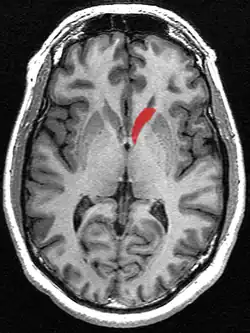

![]() Caudate nucleus (in red) shown within the brain | |

The caudate nuclei are near the center of the brain, sitting astride the thalamus. There is a caudate nucleus in each hemisphere of the brain. Each nucleus is C-shaped, with a wider "head" (caput in Latin) at the front, tapering to a "body" (corpus) and a "tail" (cauda). Sometimes a part of the caudate nucleus is called the "knee" (genu).[6] The caudate head receives its blood supply from the lenticulostriate artery; the tail of the caudate receives its blood supply from the anterior choroidal artery.[7]